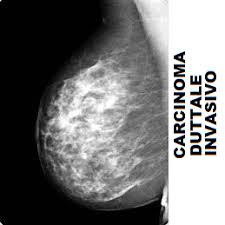

Una paziente calabrese racconta mesi di ritardi, esami mancati e silenzi istituzionali. La diagnosi di carcinoma duttale invasivo arriva solo dopo essersi rivolta al Nord.

Carcinoma duttale invasivo: tutto inizia da una cisti

Lì arriva la diagnosi: carcinoma duttale invasivo.